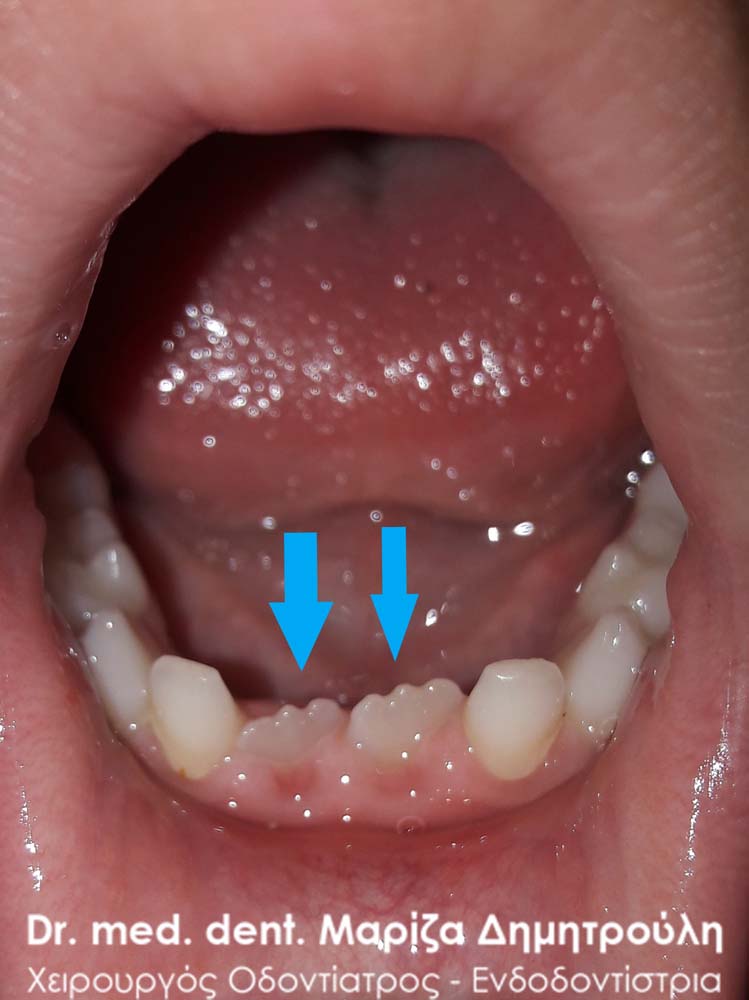

Το κοριτσάκι παραπονείται οτι πονάει κάποιες φορές στην πρόσθια περιοχή της κάτω γνάθου όταν δαγκώνει τροφές. Οι γονείς μετά από τα παράπονα του παιδιού παρατήρησαν την παραμονή του νεογιλού κάτω τομέα, παρόλο που το αντίστοιχο μόνιμο δόντι έχει ανατείλει μέσα στο στόμα. Στην προκειμένη περίπτωση απαιτείται η άμεση εξαγωγή του νεογιλού δοντιού από τον οδοντίατρο.

Περιστατικό – Εξαγωγή παιδικού δοντιού (διπλό δόντι / παραμονή νεογιλού δοντιού)

Οι γονείς παρατήρησαν οτι ο αριστερός νεογιλός τομέας δεν “κουνιέται” παρόλο που είχαν κάνει την εμφάνιση τους τα δύο μόνιμα πρόσθια κάτω δόντια. Μετά την κλινική εξέταση επιβεβαιώθηκε οτι το παιδικό δοντάκι δεν είχε καμία κινητικότητα, οπότε και αποφασίστηκε η αφαίρεση στο ιατρείο, μετά από χορήγηση τοπικής αναισθησίας.

Δεν είναι λίγες οι φορές που τα νεογιλά δόντια παραμένουν στον οδοντικό φραγμό παρόλο που τα αντίστοιχα μόνιμα δόντια έχουν ανατείλει ήδη στο στόμα του παιδιού. Στην περίπτωση αυτή είναι απαραίτητη η απομάκρυνση των παιδικών δοντιών από τον οδοντίατρο, έτσι ώστε το μόνιμο δόντι να ανατείλει πλήρως στο στόμα του παιδιού και να “πάρει” την τελική του θέση στον οδοντικό φραγμό.